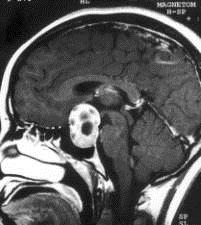

问题 病历摘要:??患者男性,35岁。性功能减退2年,视力下降6月。既往体健。体检:神清,皮肤细腻,毛发稀疏。视力左眼0.3,右眼0.5,双瞳等大等圆,直径3.5mm,对光反射稍迟钝,双颞侧偏盲,双眼底视神经乳头原发性萎缩,余神经系统未见异常。 患者出现上述情况,作何处理?提示:术后第?1日患者尿量300ml/小时,尿比重1.002

选项 A.口服卡马西平 B.口服双氢克尿塞 C.垂体后叶素皮下注射 D.静滴地塞米松 E.口服弥凝 F.肌注长效尿崩停 G.口服安体舒通

答案 C